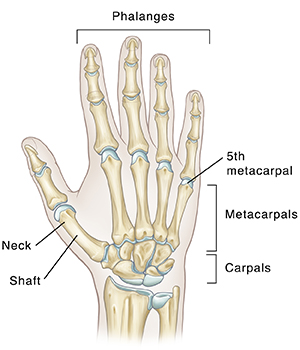

Understanding the bones of the hand

The bones of your hand are called metacarpal bones. They connect the bones of your fingers (phalanges) to the bones of your wrist (carpals). The fifth metacarpal is the metacarpal of the fifth finger (pinky). A metacarpal bone has a long section of the bone (shaft) connected to the end of the bone. The area where the shaft connects to the end of the bone is called the neck. The neck is the weakest point of the bone. This is where a boxer’s fracture happens.